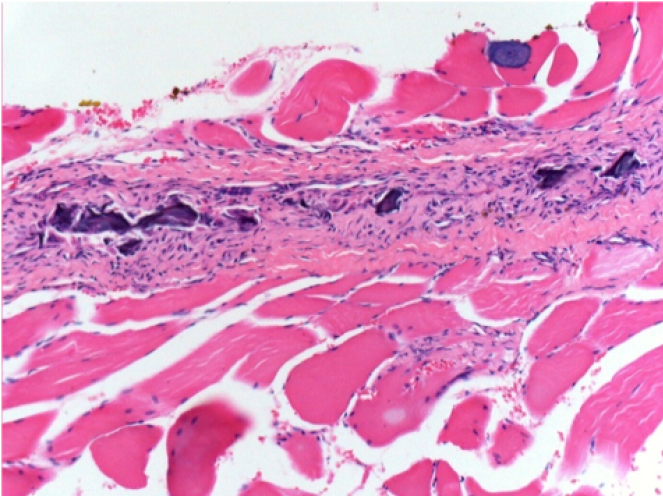

10 Inyección subcutánea

0,5 ml (5 x 0,1 ml) Endopeel SC Inyección en el área pretibial subcutánea derecha.

L:200x-Control-SC

R-D10-SC-200X

R-D30-SC-200X

R-D90-SC-200X

R-D210-SC-200X

R-D210-SC-400X